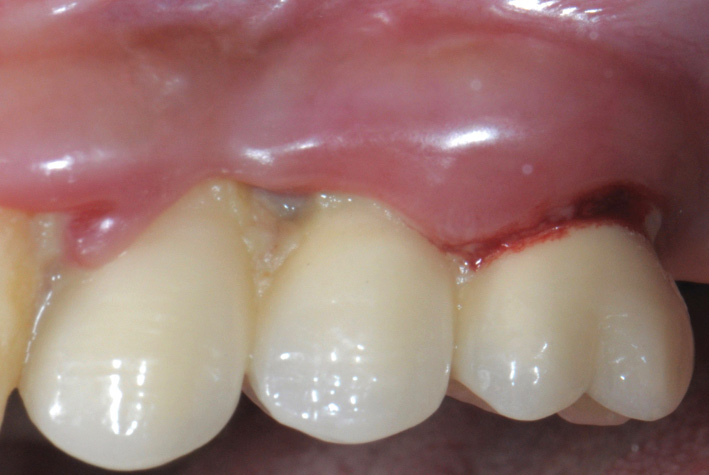

The first step in preventive strategies must be to perform a correct diagnosis of the peri-implant condition by accurately assessing the health of the peri-implant hard and soft tissues through periodontal probing and periapical radiographs at the time of definitive prosthetic installation. These measurements should be considered the baseline diagnosis and, therefore, represent a true starting point for evaluating the changes on the radiographic bone levels and probing pocket depths (PPD) at future recall appointments (Figure 1 and Figure 2).6 Although probing depth measurements of peri-implant tissues do not have the same diagnostic value as probing periodontal tissues, there is evidence that BOP is the most objective sign of peri-implant tissue inflammation; significant deepening of PPD compared with baseline measurements is also a sign of disease that indicates the need to perform a radiographic evaluation (Figure 3 through Figure 5).6,10,11

Fig 1. Baseline measurements at the time of prosthetic delivery: probing pocket depth and

Figure 1

Fig 2. periapical radiographs.

Figure 2

Fig 3. Peri-implant mucositis: mucosal inflammation.

Figure 3

Fig 4. Bleeding on probing.

Figure 4

Fig 5. Radiograph showing no bone loss.

Figure 5